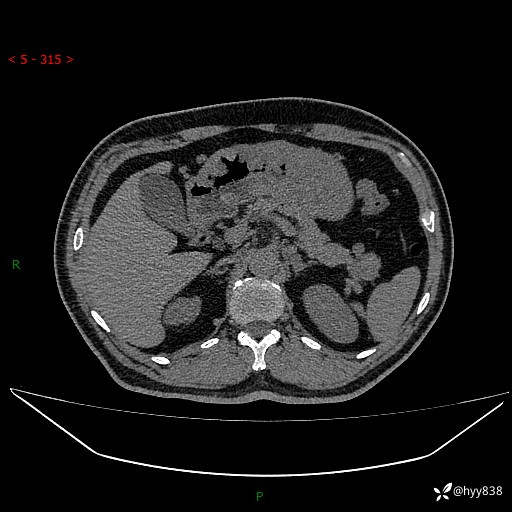

增强动脉期